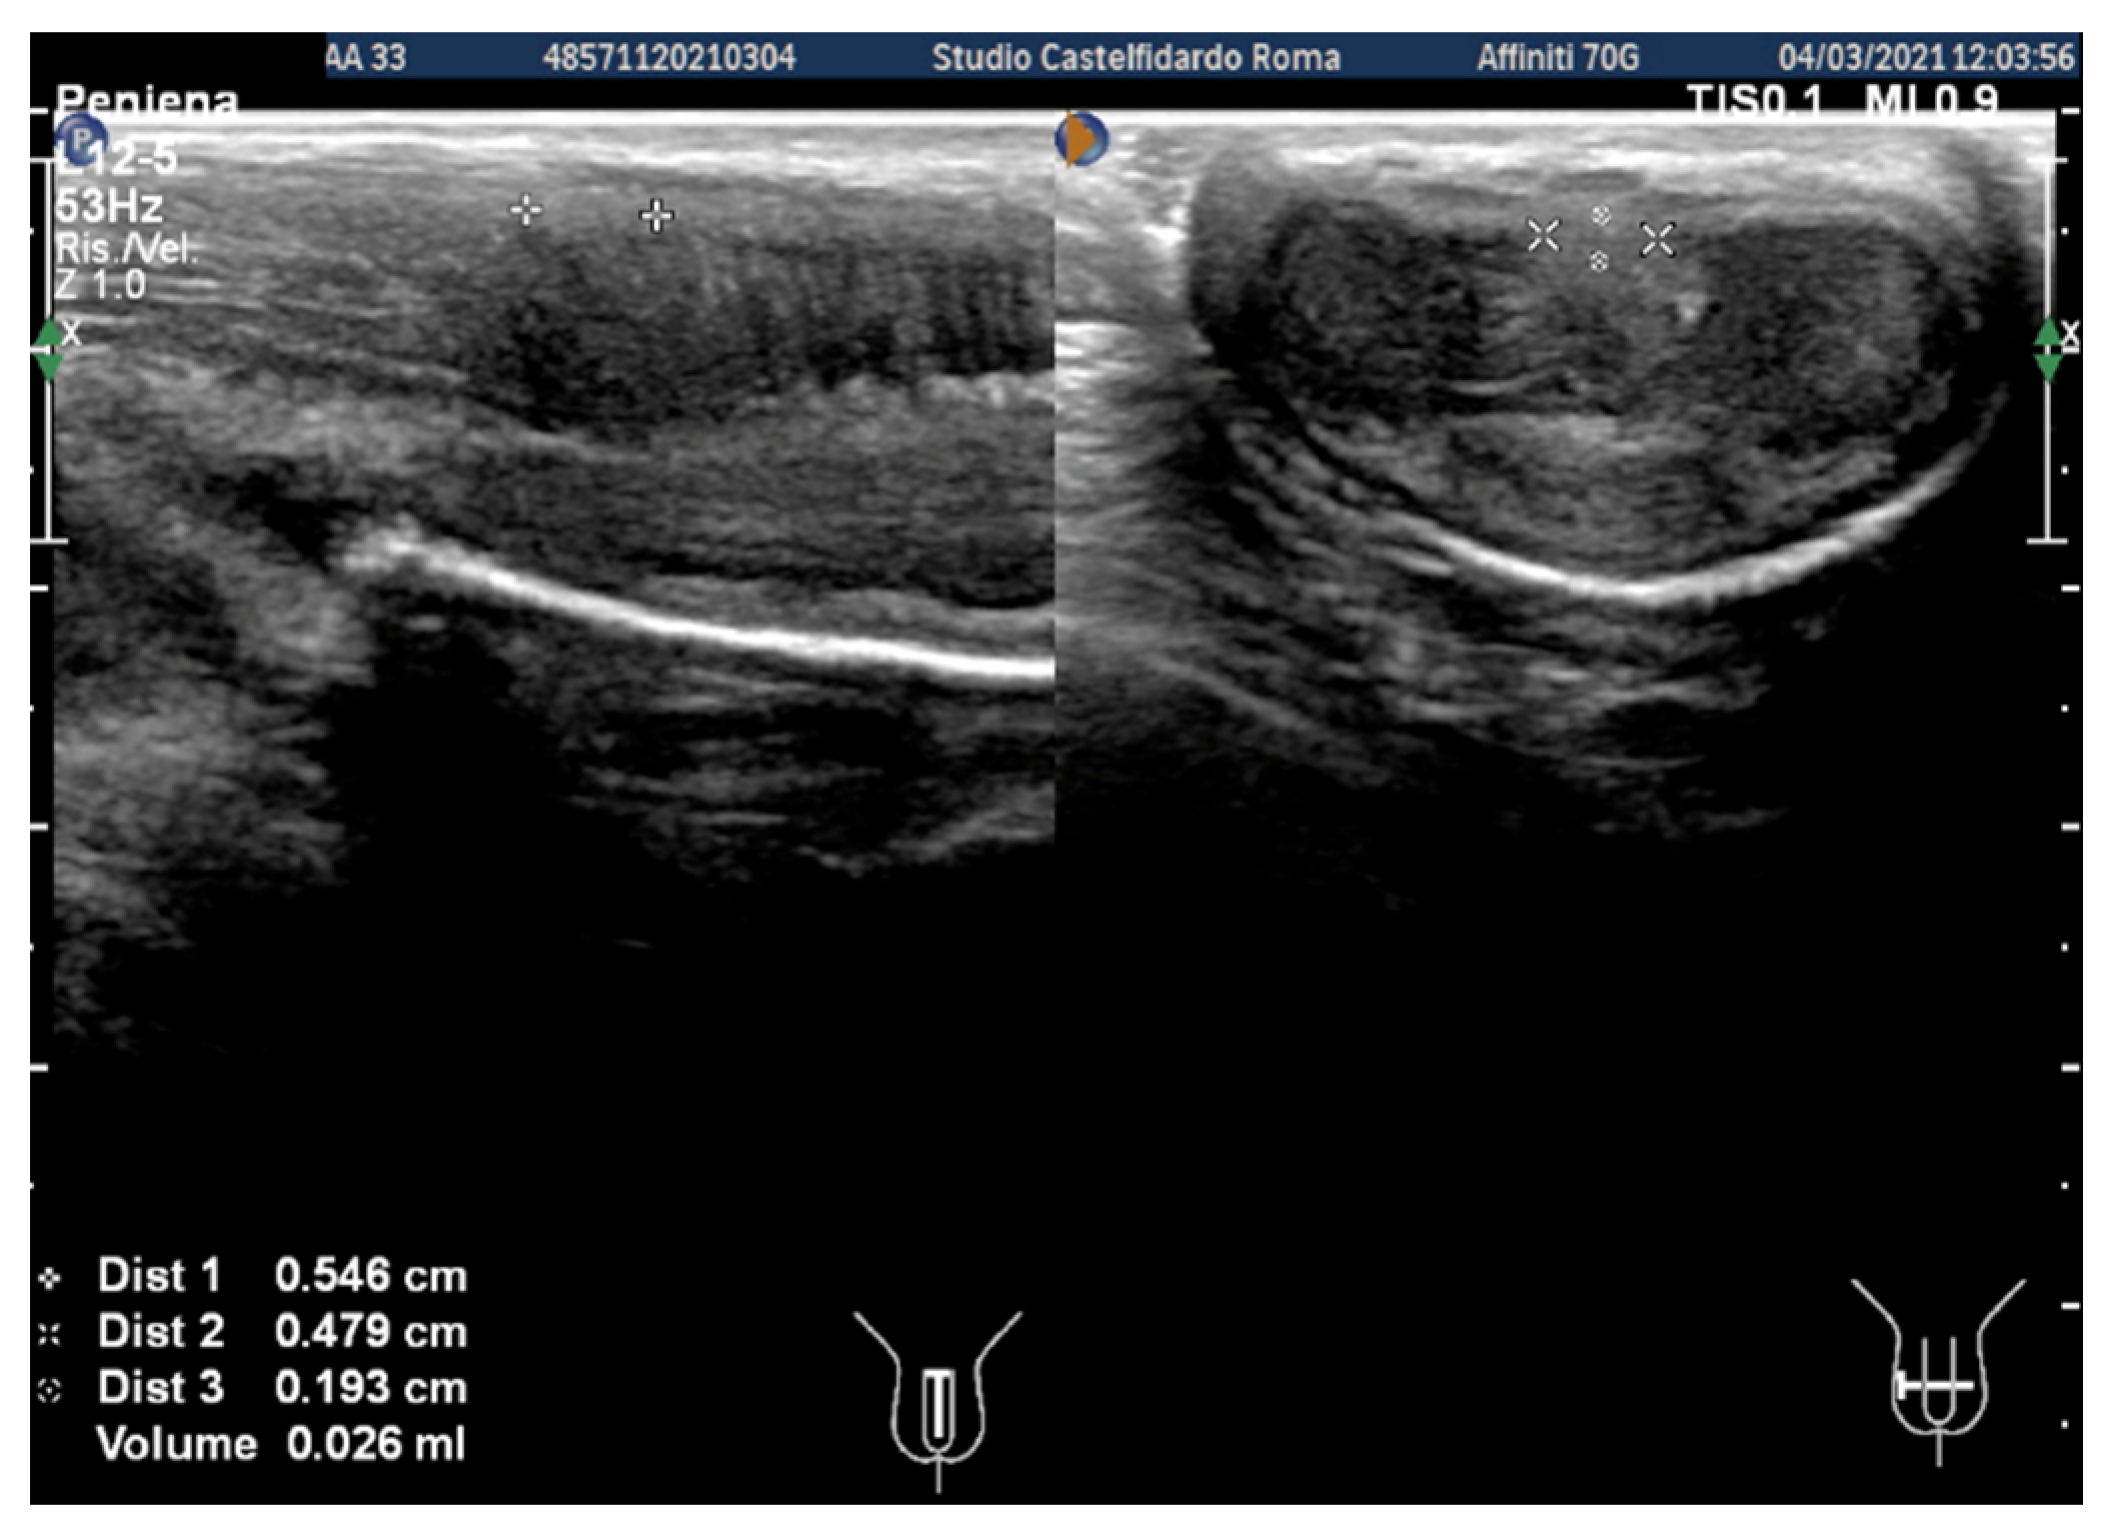

| 1 | 31 years | Chronic prostatitis and associated anxious and depressive state. | Distal third | (A) 15.1 × 12.1 × 3.7 mm volume = 353 mm3 (B) No plaque detected | (A) 10-degree ventral curvature + 15-degree left curvature (B) None | VAS score = 8 Pain disappeared after 12 months | 26 > 27 | 30 months | Orally: propolis 600 mg + bilberry 160 mg + silymarin 400 mg + ginkgo biloba 250 mg + L-carnitine 1000 mg + coenzyme Q10 100 mg + Boswellia 200 mg + Vitamin E 30 mg/daily/for 30 months + topically: diclofenac gel 4%/2× daily for 30 months Note: The patient refused periplaque penile injections with pentoxifylline |